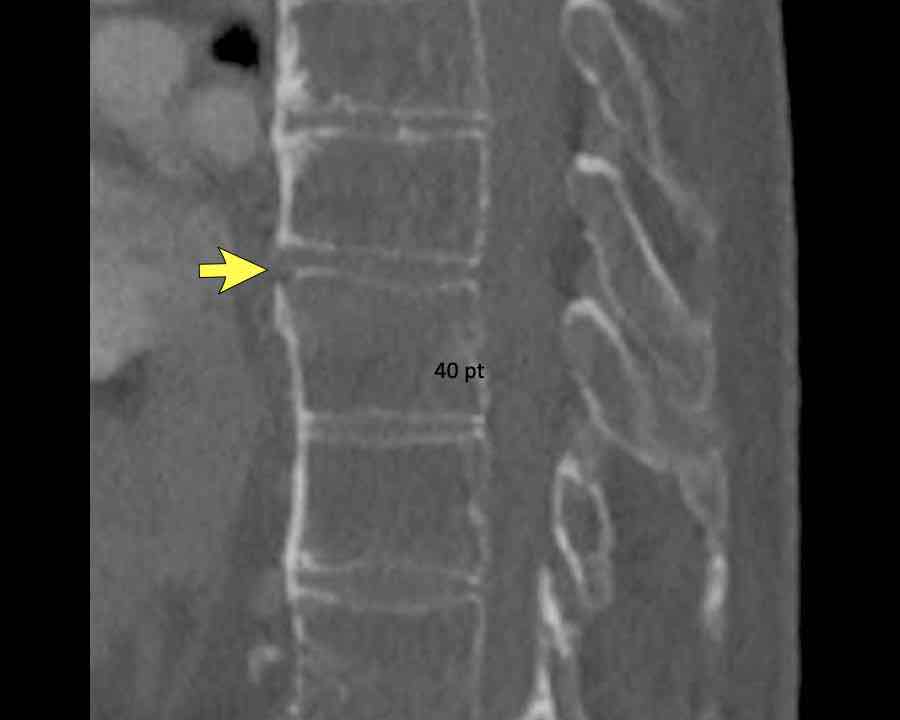

Scroll through images.

What are the findings?

Findings

- C injury? No.

- Signs of a rigid spine?

Yes, so be aware of potentially very subtle B3 injury. - A subtle fracture on the anterior vertebral body is seen (arrows).

Conclusion

Injury type B3.